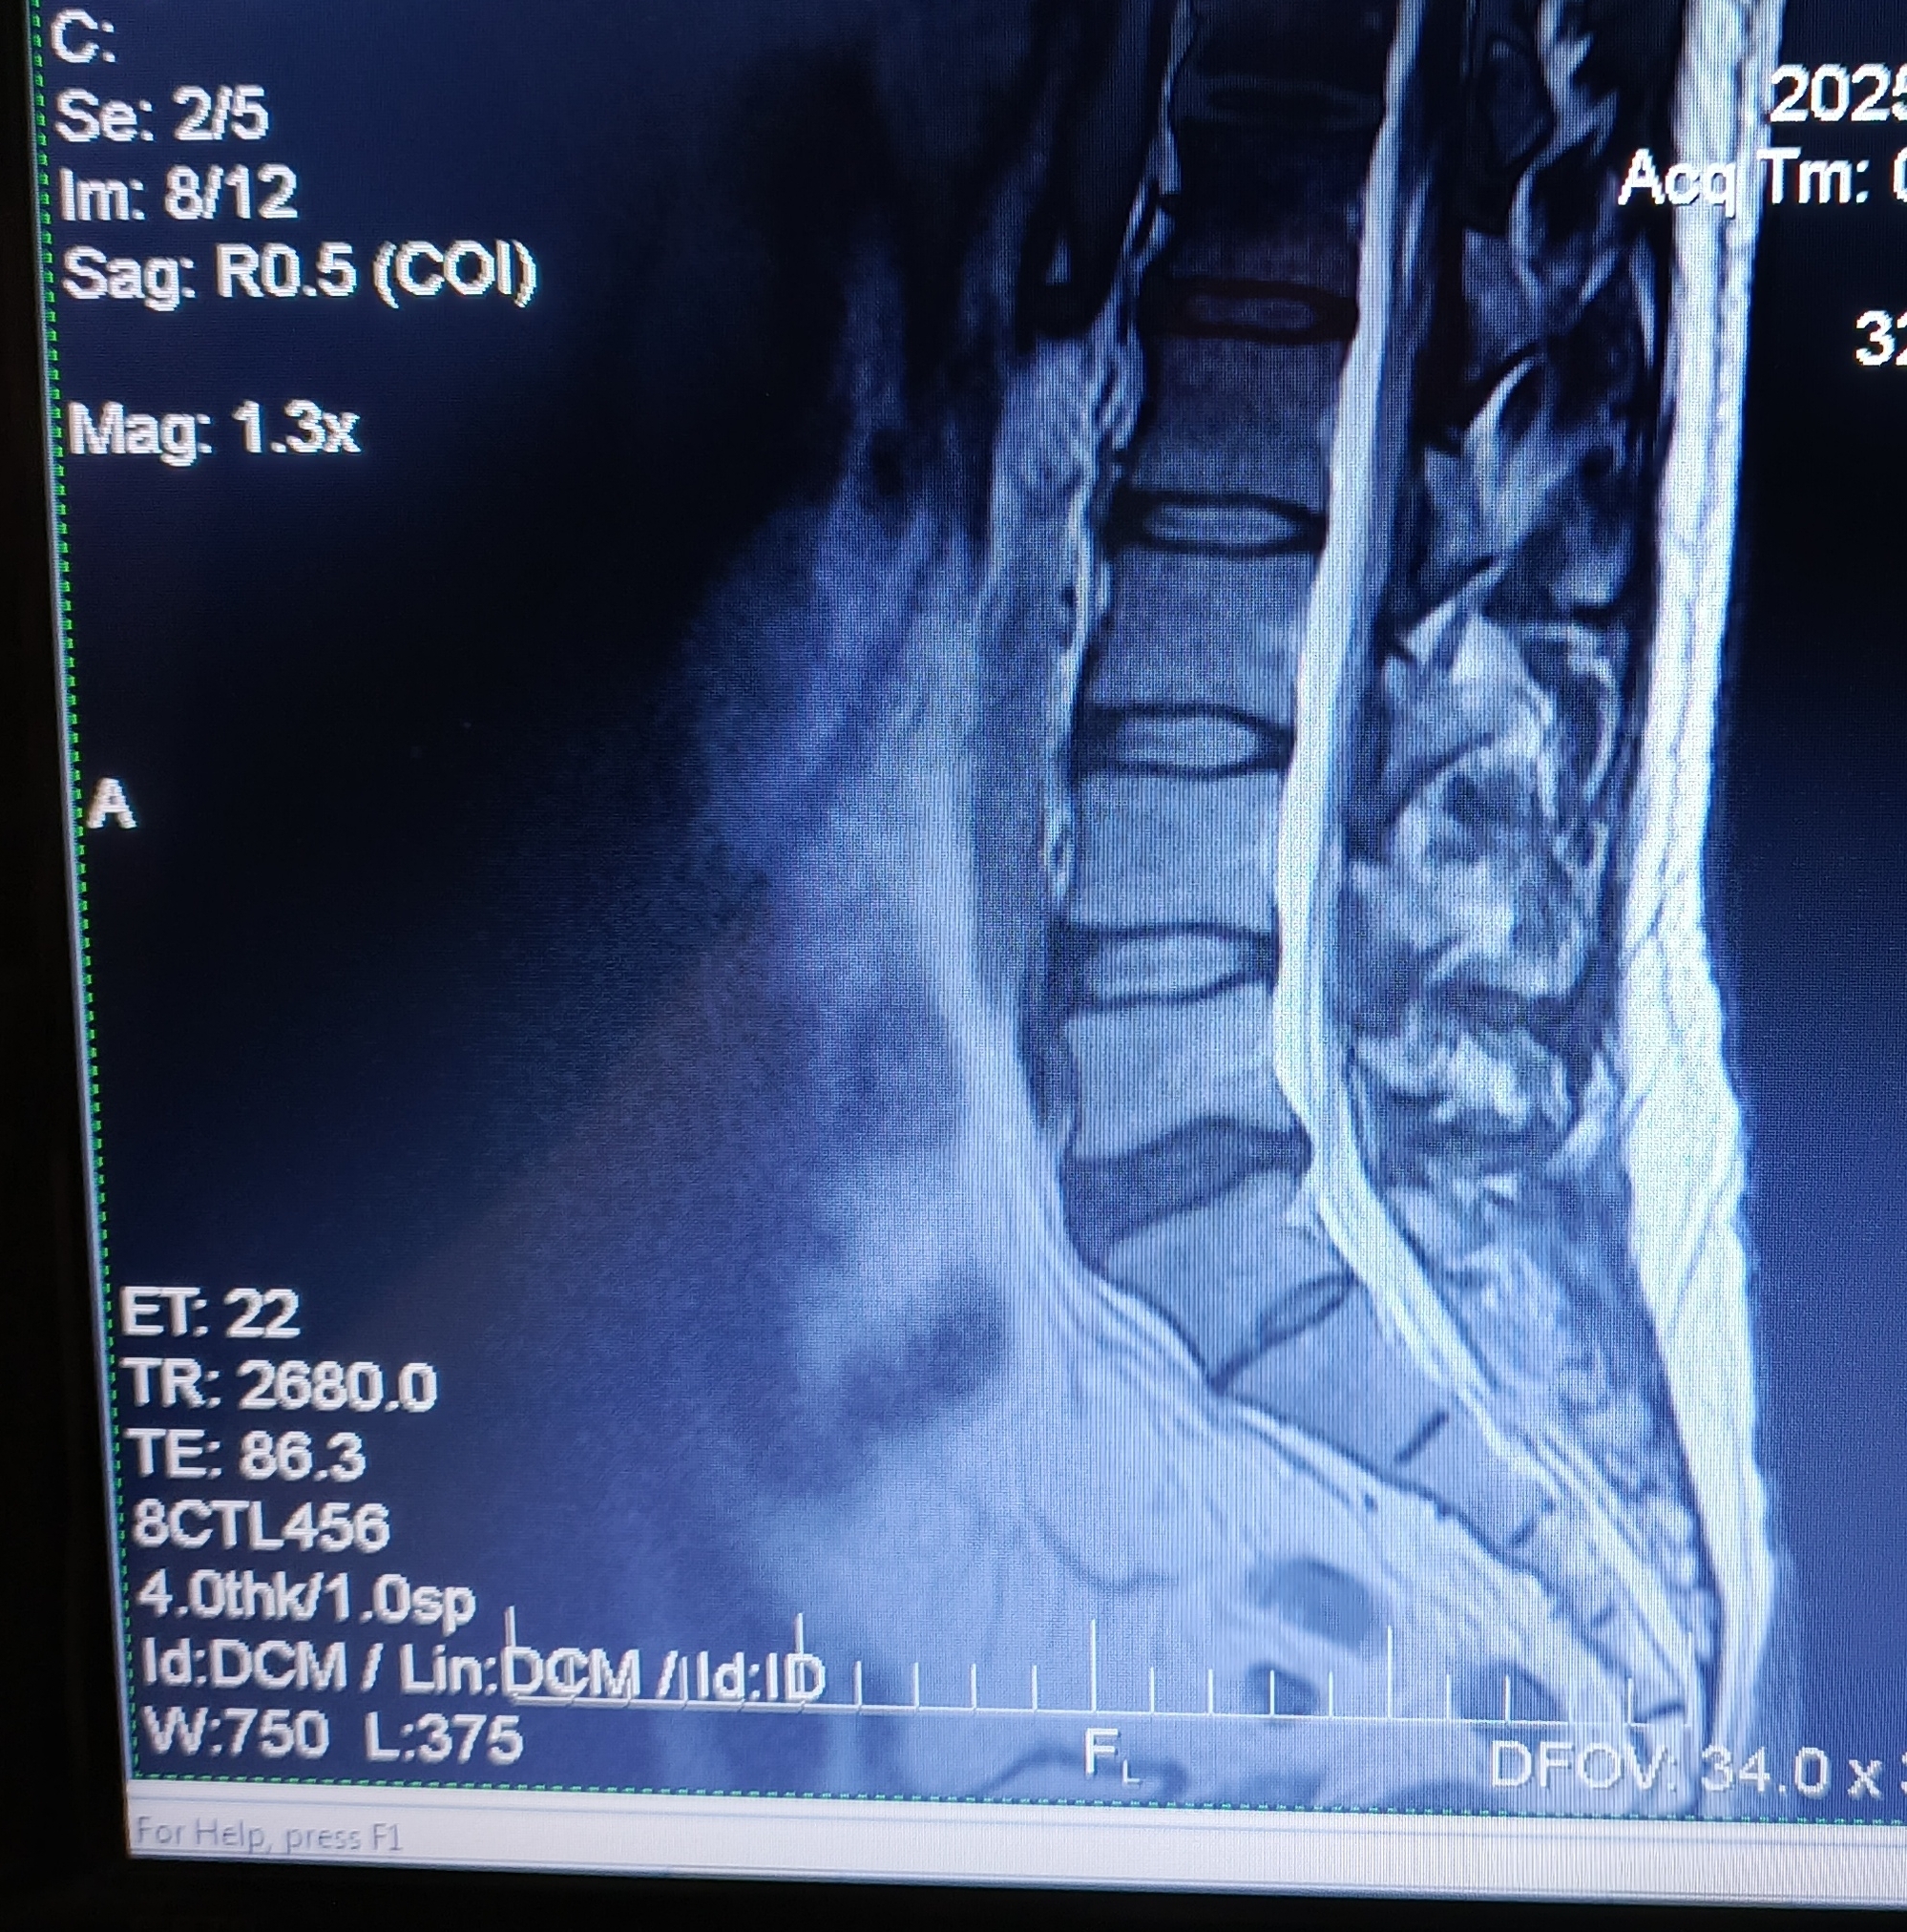

Есть боли в ПОП, в 2020 году на основании МРТ был поставлен диагноз: "Грыжа диска L5/S1. Протрузия диска L4/5."

В 2024 году во время очередного обострения делал повторно МРТ. Диагноз: "Грыжа диска L5/S1. Протрузия диска L4/5. При сравнении с данными 2020 года динамика отрицательная."

2025 год. После очередного обострения и стандартного лечения острая боль прошла, но остались тупые тянущие боли. На днях сделал повторно МРТ. Диагноз: умеренный остеохондроз, с поражением диска L5/S1 с диффузно медианной протрузией.

Собственно вопрос, к тем кто разбирается, действительно ли на данных снимках нет грыжи?

Снимки (с экрана) ниже. Откликнувшихся заранее благодарю.